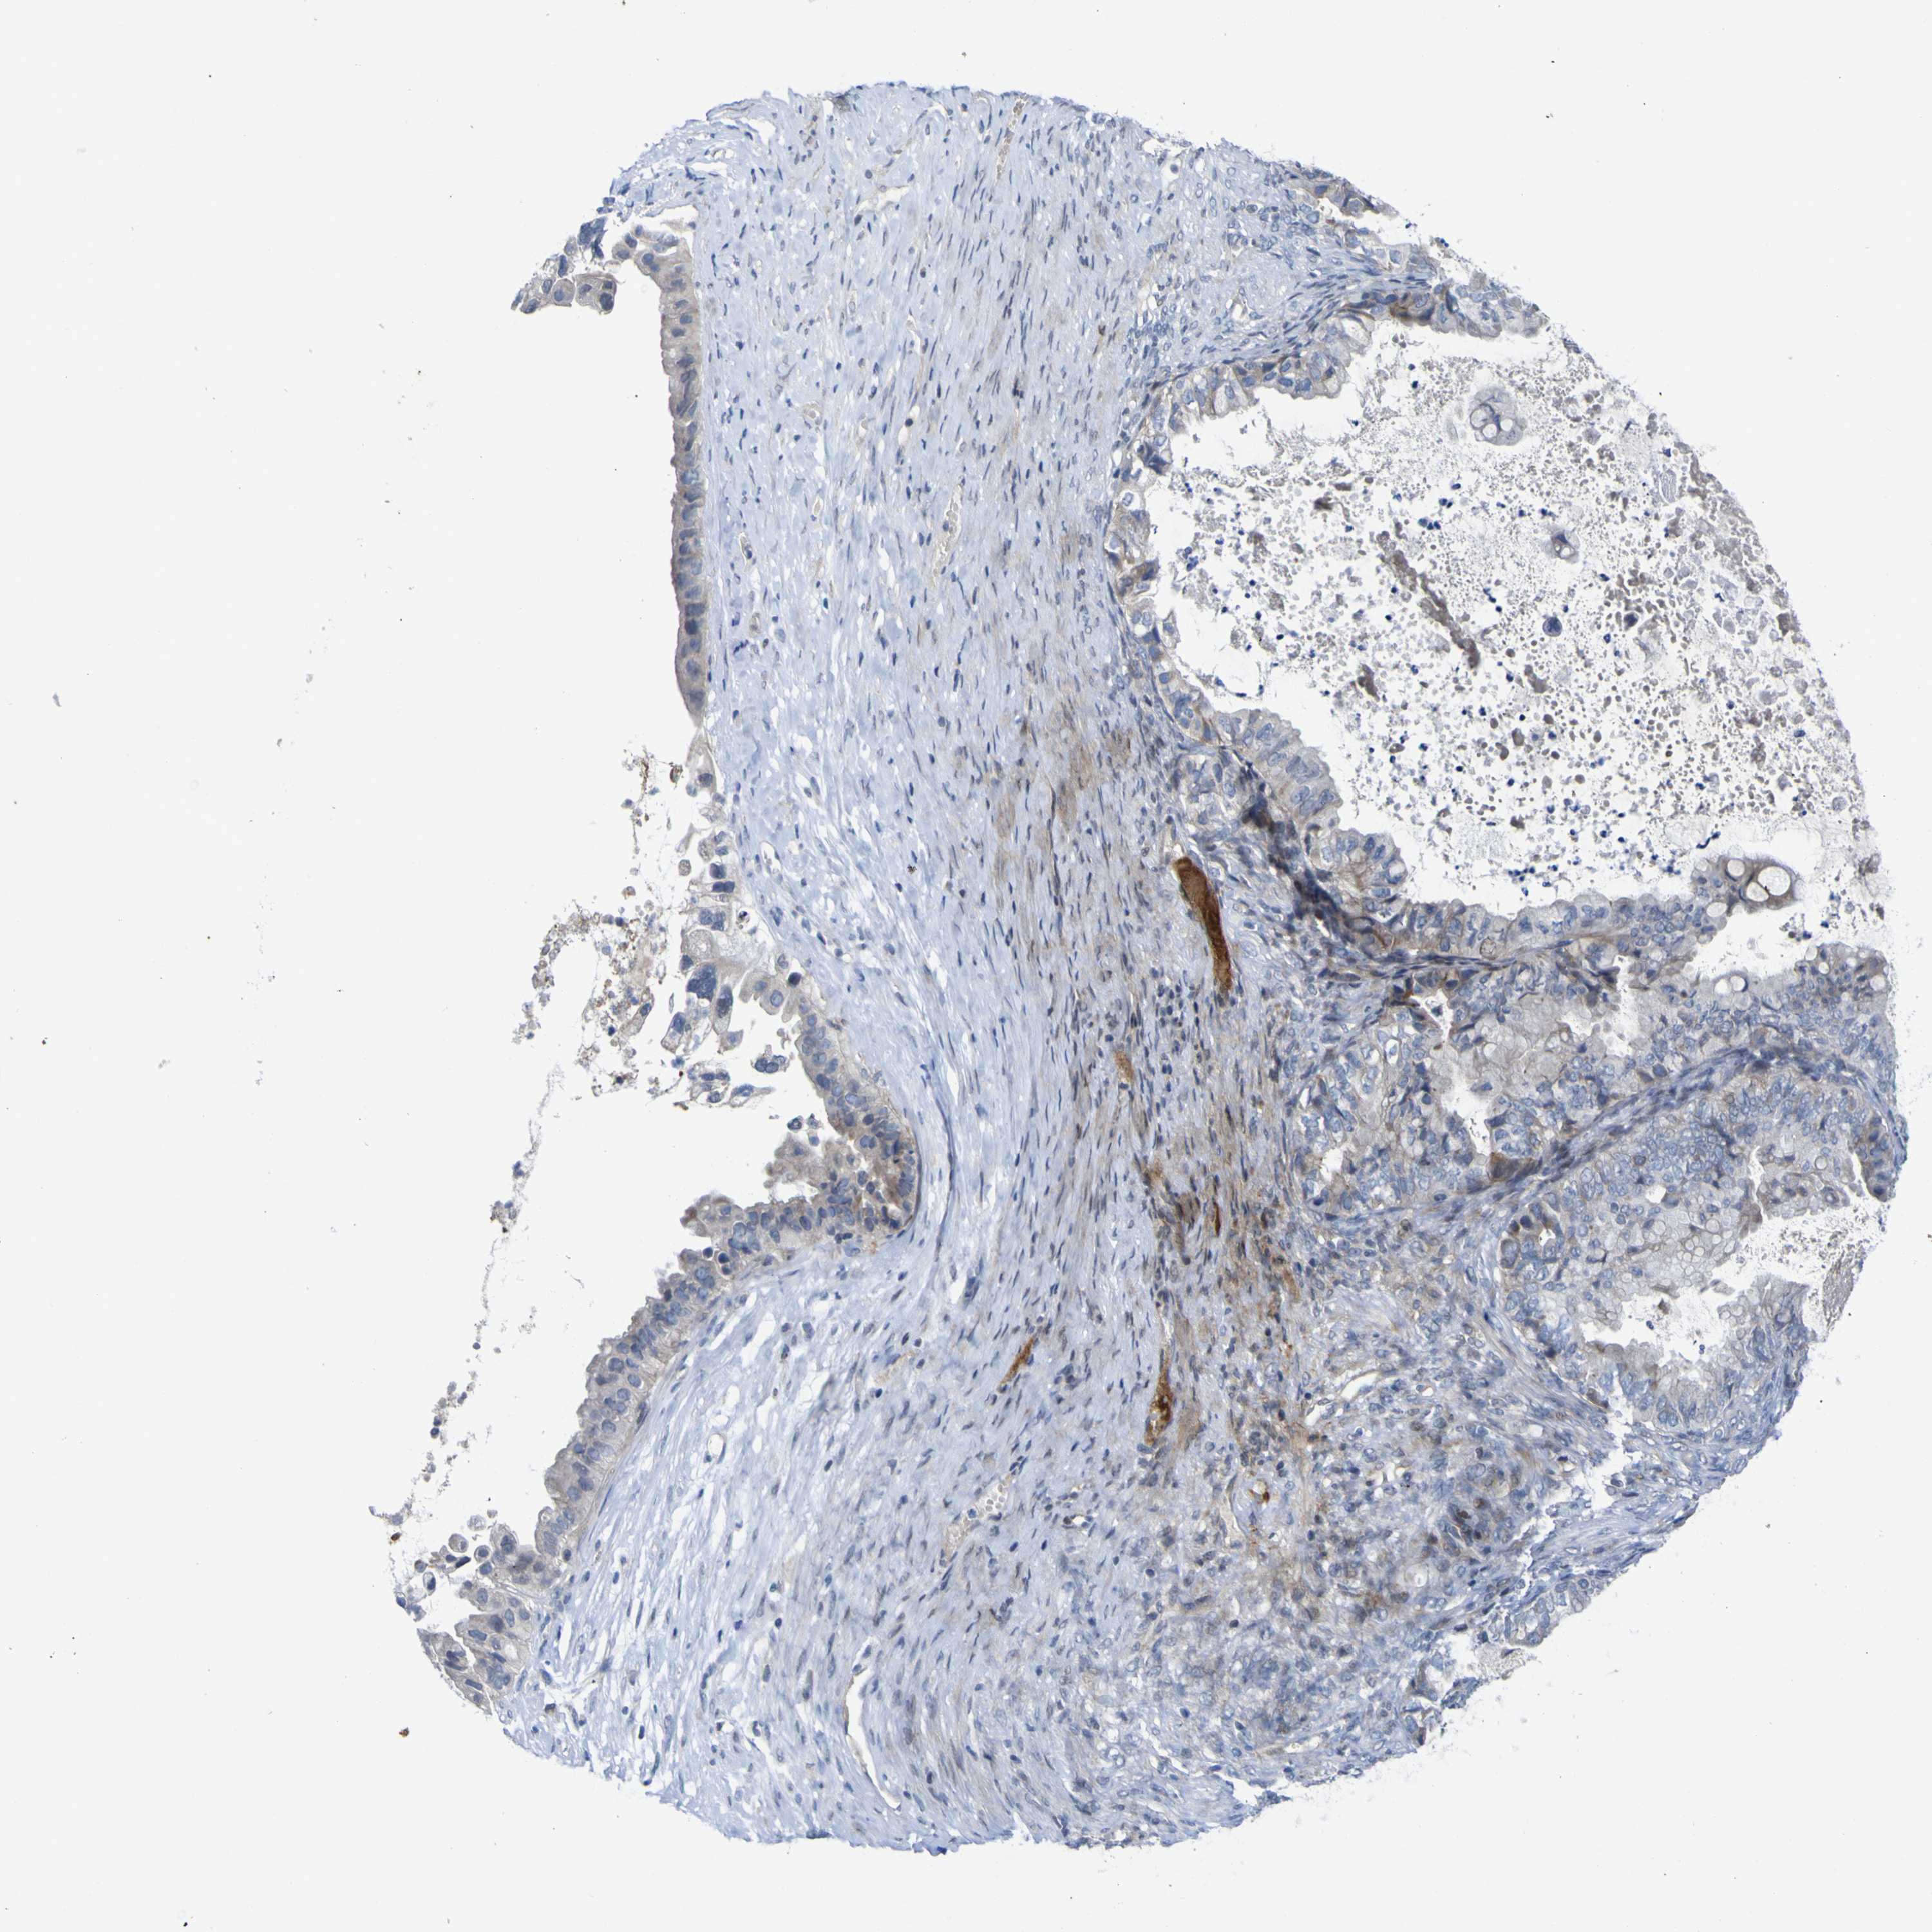

OVARIAN CANCER - Protein expressioni

A mouse-over function shows sample information and annotation data. Click on an image to view it in a full screen mode. Samples can be filtered based on level of antibody staining by selecting one or several of the following categories: high, medium, low and not detected. The assay and annotation is described here.

Note that samples used for immunohistochemistry by the Human Protein Atlas do not correspond to samples in the TCGA dataset.

Antibody stainingi

Antibody staining in the annotated cell types in the current human tissue is reported as not detected, low, medium, or high, based on conventional immunohistochemistry profiling in selected tissues. This score is based on the combination of the staining intensity and fraction of stained cells.

Each image is clickable and will lead to virtual microscopy that enables deeper exploration of all samples and also displays staining intensity scores, fraction scores and subcellular localization as well as patient and tissue information for each sample.

Antibody HPA027887

Carcinoma, endometroid